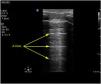

A high-frequency linear probe is used for this measurement, positioned at the last intercostal spaces (we place the probe on the anterior axillary line, generally perpendicular to intercostal spaces 7-8, 8-9 and 9-10, with the probe covering two ribs in order to visualize the diaphragm apposition zone)(Suppl. Fig. 13), ideally with the patient in the supine position. A somewhat more posterior position of the probe has also been described, between the anterior and mid-axillary lines. In this way, we locate the “apposition zone” where the diaphragm inserts into the chest wall. The diaphragm is identified as a hypoechoic band delimited by two hyperechoic lines corresponding to the pleura and peritoneum (Suppl. Fig. 14).22,31–35

The measurement of diaphragmatic thickness is made at the end of unforced expiration. It is advisable to record at least three images for the calculation. The normality reference figures vary among the different studies.35 A study of 109 healthy individuals reported normality figures of 0.16 ± 0.04 cm, with a mean value of 0.14 ± 0.03 cm in women and 0.19 ± 0.04 cm in men (Suppl. Fig. 15).36